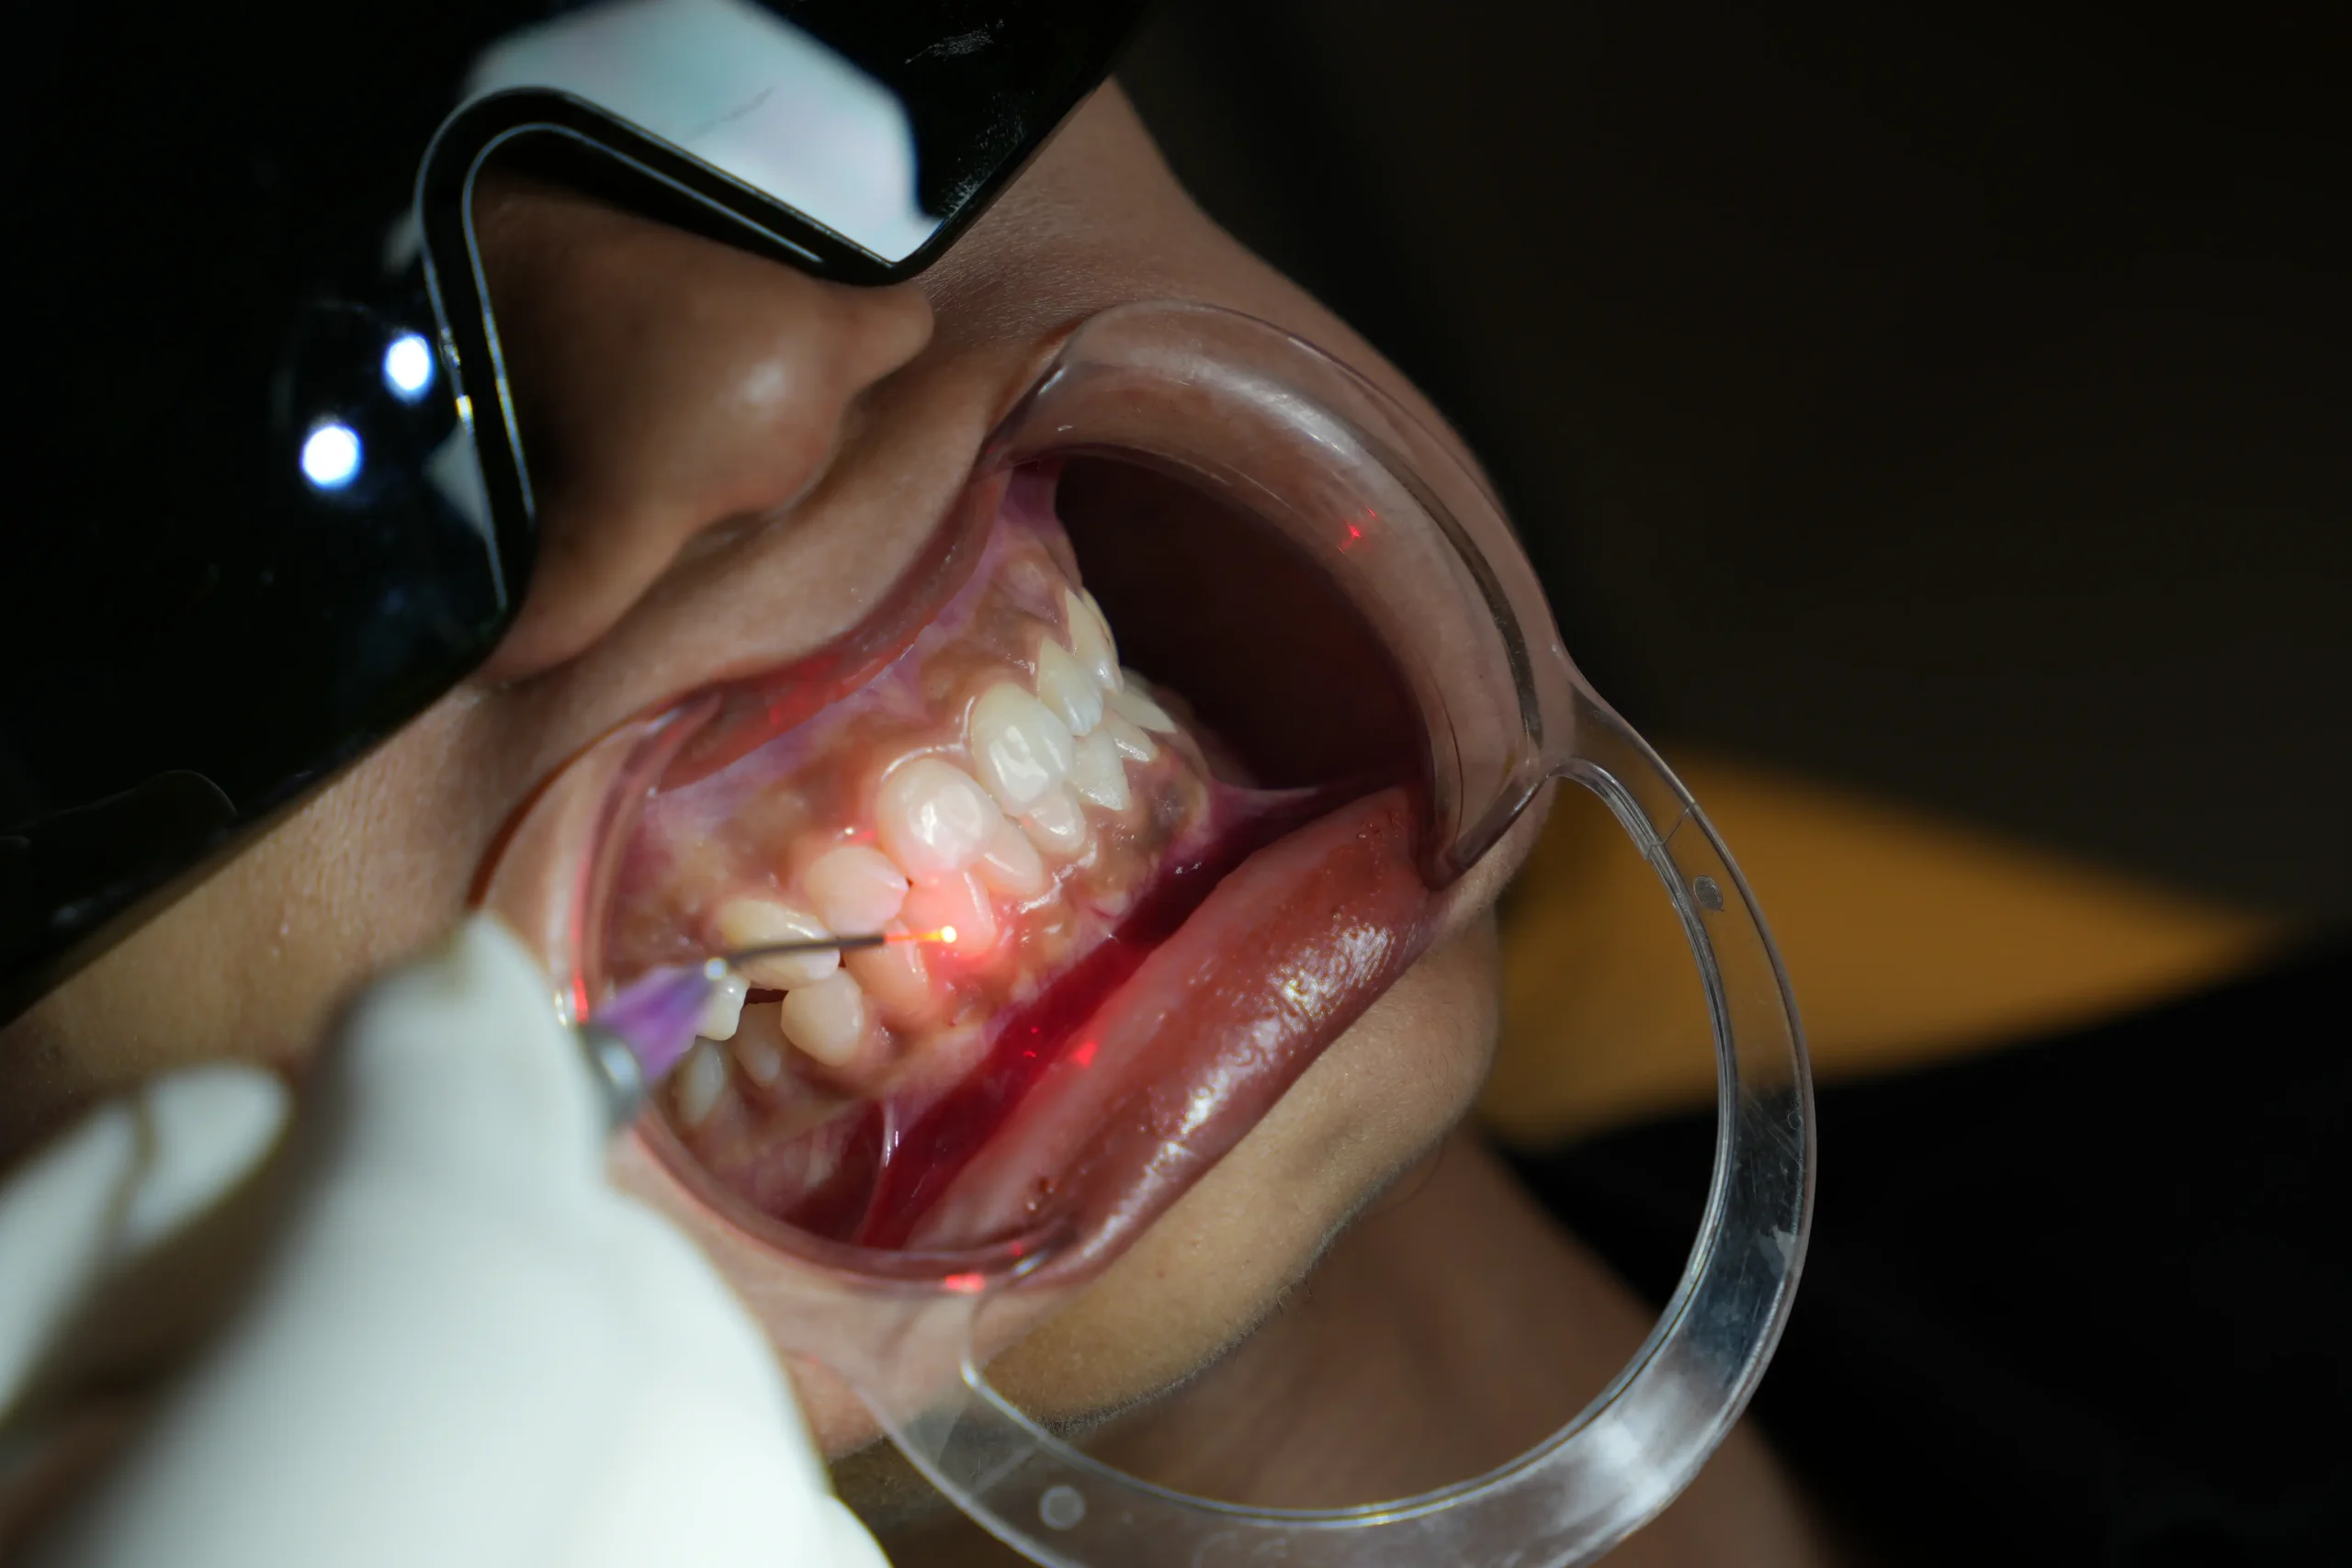

The treatment area is carefully cleaned and prepared. Protective eyewear is provided for eye safety during laser use, and in most cases, little to no anaesthesia is required.

Focused laser energy is used to gently reshape, remove, or disinfect tissue with high precision.